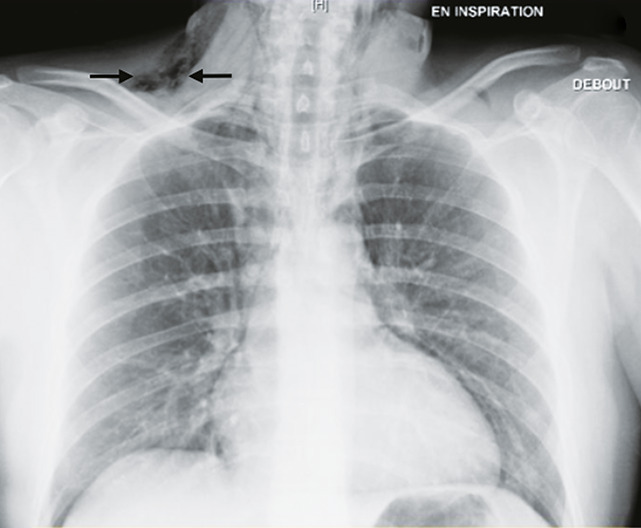

Un homme de 25 ans, sans autre antécédent qu’un tabagisme actif, a ressenti, au décours d’un repas, une douleur cervicale accentuée par la déglutition et une sensation de gêne respiratoire. Il décrivait une atteinte rhinopharyngée peu intense avec une toux grasse depuis 48 heures. Aux urgences, son état hémodynamique n’inspirait pas d’inquiétude, avec une pression artérielle à 151/85 mmHg, une fréquence cardiaque à 90 batt/min, une saturation en oxygène en air ambiant à 95 % et une fréquence respiratoire à 20 cycles/min. Il n’existait pas de notion d’effort à glotte fermée, ni de prise de toxique. L’examen clinique a révélé une rhinopharyngite banale mais surtout un emphysème sous-cutané sus-claviculaire droit (signe de Minnigerode : présence d’air dans la région para-œsophagienne du cou). La radiographie thoracique a mis en évidence un emphysème sous-cutané ainsi qu’un pneumomédiastin (fig. 1 et 2 ). Le patient a été hospitalisé 24 heures dans un service de post-urgence pour surveillance et prise en charge de la douleur. Le scanner thoracique, réalisé le lendemain, a confirmé un pneumo-médiastin de faible abondance ainsi qu’un minime pneumothorax scissural gauche (fig. 3 ). L’état de santé du patient a été réévalué en consultation de pneumologie quatre jours plus tard. L’évolution a été favorable.

Le pneumomédiastin est rare (incidence : 4/100 000) et plus encore s’il est associé à un pneumothorax (1,5 % des pneumomédiastins),1, 2 comme dans le cas de ce patient. L’augmentation de la pression dans les voies respiratoires peut être responsable de pneumomédiastin.3 L’imagerie confirme le diagnostic, notamment la radiographie thoracique. Cette pathologie, très souvent bénigne, nécessite un traitement antalgique et une surveillance simple.